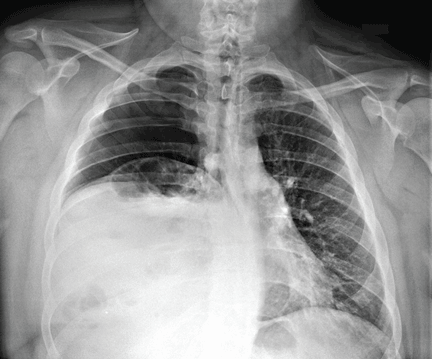

Radiography shows a large right pneumothorax and an elevated right diaphragm (Figure 1). Computed tomography (CT) (Figure 2) reveals a right anterior apical pneumothorax with hypoplastic lung and significant elevation of the right diaphragm with fat, bowel, and kidney within the right thorax. He is hemodynamically stable and shows no signs of bowel obstruction.

Plain radiography shows a large right pneumothorax and an elevated right diaphragm.